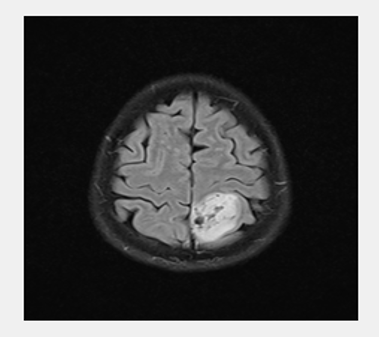

DL stands for disciplines of Artificial Intelligence (AI) that learn characteristics and spot patterns in data using neural networks. Images and other grid-like data are processed using CNNs, which are specialized DL architectures (Alqudah et al., 2020; Sharma et al., 2020). Starting with basic patterns like edges and working their way up to more intricate structures like tumor borders in Figure 1, they employ convolutional layers to extract characteristics in a hierarchical manner. Because CNNs can analyze huge volumes of image data fast and lessen the need for manual feature extraction, they have shown remarkable efficacy in medical imaging for tumor identification and classification (Rasool et al., 2022). CNNs can recognize patterns that distinguish between healthy and diseased tissues, including pituitary tumors, meningiomas, and gliomas, by training on labeled datasets.

This proposed model used the Kaggle dataset to test the suggested methods. The two categories of this dataset were testing and training. Glioma tumor, meningioma tumor, pituitary tumor, and non-tumor photos were all included in each training and testing set. The testing set consisted of 394 images, while the training set comprised 2,870 images. Data preprocessing techniques like brain stripping enhanced descriptions of data. Glioma, meningioma, non-tumor, and pituitary tumors were the categories for performance evaluation. Examples of several tumor categories in various locations are depicted in Figure 6 (Bhuvaji, 2020).